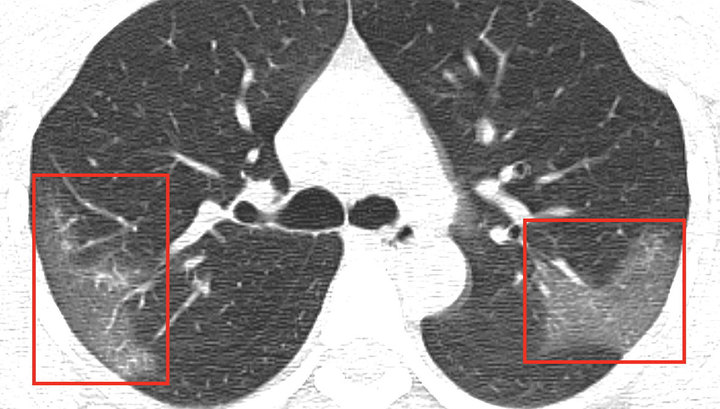

Новый коронавирус поражает ткани легких в три раза сильнее, чем атипичная пневмония (тяжелый острый респираторный синдром — ТОРС), сообщила группа ученых под руководством профессора Юэн Квок-юна из Университета Гонконга.

У шести добровольцев взяли образцы легочной ткани. Выяснилось, что за 2 суток вирус реплицировался в 3,2 раза сильнее, чем вирус атипичной пневмонии и почти не спровоцировал действие сигнальных белков иммунной системы.

Коронавирус размножается в условиях пониженного уровня интерферонов и воспалительных реакций, отметил доктор Джаспер Чан. Профессор Юэн Квок-юн заявил, что шансов сдержать пандемию до июля, почти нет, передает ТАСС.